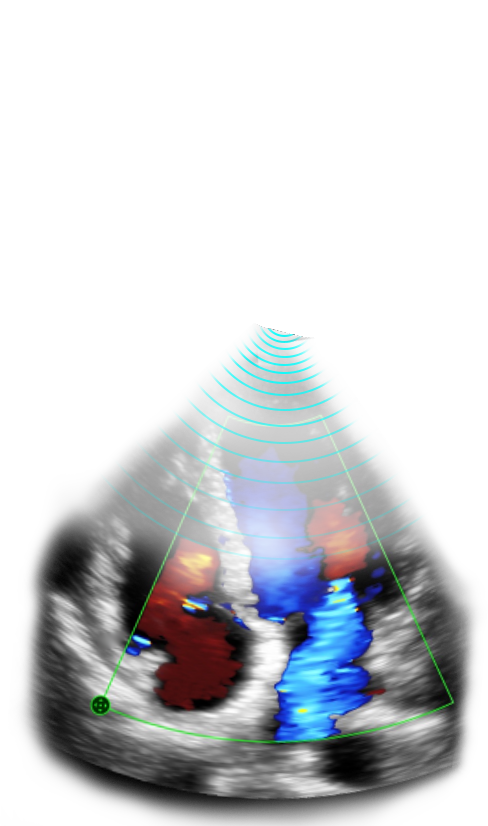

Immagini cliniche

Rigurgito mitrale e tricuspidale

Immagini cliniche

Rigurgito mitrale e tricuspidale